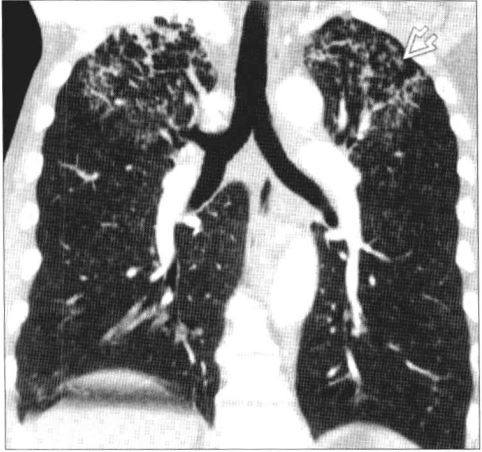

如果我们的机体免疫未能迅速形成足够有效的防疫体系,那么我们的免疫细胞与结核杆菌就会呈现出僵持状态,谁也不能彻底击败谁,在我们体内就可能表现为一些结核球、陈旧纤维病灶等等,但因为巨噬细胞内仍可残留一些静止状态的结核杆菌,往后如果人体免疫下降时,结核杆菌就会重新大量繁殖,结核病重新活动,肺部可逐步表现出结核病活动的痕迹,例如原来陈旧的结核病灶周围可出现新的病灶、结核球周围出现新的病灶。

如果我们的免疫力很差,那么我们的免疫细胞就只能被结核杆菌按着摩擦,结核在体内肆意生长,可以表现为各种形式:结核性脑膜炎、骨结核、毁损肺、结核性胸膜炎等等……